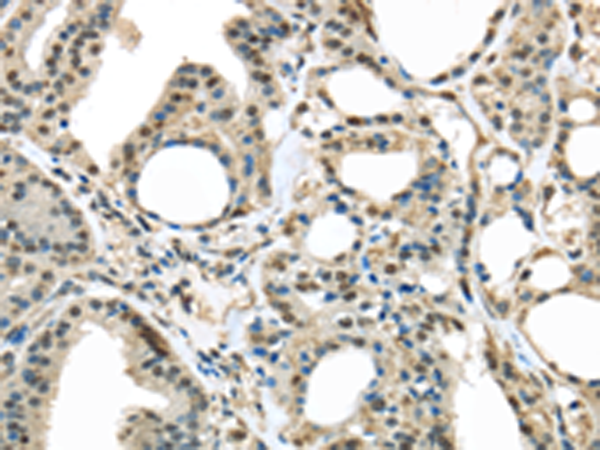

分类: 科研抗体货号: P08885别名: MSP; MSPL; MSPS; TMPRSS11应用: IHC反应种属: Human, Mouse